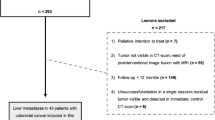

Study population

The data from the previously reported patient cohort for which the minimum margin size was already assessed using the 2D manual method described above was used for evaluation. The patients were reported in an investigation of the factors affecting the oncological outcomes of RFA of CRLMs [9], in which treatments of 233 CRLMs were analyzed, and the minimum margin was measured in 174 CRLMs. These 174 CRLMs from 130 consecutive patients who were treated between December 2002 and December 2012, with either CT or positron emission tomography/CT guidance, made up the potentially eligible patients cohort used in the current study. In our study, the data from patients were utilized solely to evaluate a new volumetric 3D margin assessment technique.

Additional exclusion criteria were utilized to determine the final cohort for this study, including (1) follow-up time is less than 2 years, and LTP did not develop; (2) multi-focal progression pattern; (3) data image format is incompatible with 3D processing; and (4) CT image slice thickness greater than 5 mm. When either pre- or post-RFA images were stored as image captures imported from the outside institutions, such data could not be processed and were defined as incompatible.

After applying the exclusion criteria described above, 108 out of 174 (62%) CRLMs were eligible for 3D assessment evaluation (Fig. 2). In 15 of these eligible cases (13.8%), rigid registration did not ensure optimal image alignment. Complete 3D assessment was performed in 93 CRLMs in a total of 72 patients (Table 1). An example of visualization of the results of 3D assessment is shown in Fig. 3. The average time to perform 3D volumetric margin analysis was 4.26 ± 1.5 min for each ablation site.